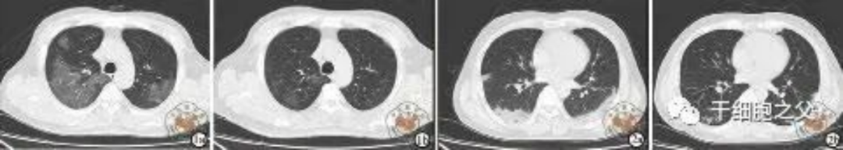

與安慰劑組相比,人臍帶間充質(zhì)干細(xì)胞修復(fù)組全肺病變體積改善了10.8%,并且人臍帶間充質(zhì)干細(xì)胞修復(fù)組在每一個(gè)隨訪節(jié)點(diǎn)都顯示出固體組分病變體積比例減少。此外,人臍帶間充質(zhì)干細(xì)胞組有17.9%的患者在12個(gè)月時(shí)CT圖像變?yōu)檎#参縿┙M沒有。

研究結(jié)果:細(xì)胞輸注后,炎癥指標(biāo)改善,復(fù)查胸部CT提示雙肺病灶較前吸收,呼吸道癥狀改善,新型冠狀病毒核酸檢測(cè)連續(xù)2次陰性,治愈出院。